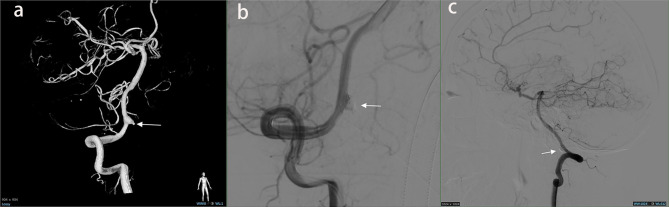

背景:颅内动脉瘤破裂合并颈内动脉闭塞(ICAO)是一种罕见且严重的血管疾病。我们的目的是描述这些患者的临床特征和结果。方法:回顾性分析中国多中心动脉瘤数据库(CMAD)中RIA合并自发性ICAO的病例。采用Logistic回归分析确定与患者预后相关的独立危险因素。采用Cox比例风险模型确定累积死亡率的预测因子。结果:我们分析了52例伴有ICAO的RIA,其中单侧41例,双侧11例。单侧ICAO病例中,同侧8例,对侧16例,中线17例。治疗包括绕线31例,夹持6例,保守处理15例。26例预后良好,17例预后不良,包括12例死亡。Logistic回归发现Hunt-Hess分级IV-V、保守治疗和症状性脑梗死是不良结局的独立危险因素。Cox比例风险模型发现Hunt-Hess分级IV-V是2年随访期间死亡率的预测因子。结论:Hunt-Hess分级、治疗和住院脑梗死独立预测不良结局,IV-V级与早期死亡相关。ICAO可能增加动脉瘤破裂的风险,突出了动脉瘤位置及其相关血流动力学机制在临床管理中的重要性。

Results: We analyzed 52 cases of RIA with ICAO, including 41 unilateral and 11 bilateral cases. Among unilateral ICAO cases, aneurysms were ipsilateral in 8, contralateral in 16, and midline in 17. Treatment included coiling (31 cases), clipping (6 cases), and conservative management (15 cases). Prognosis was favorable in 26 cases and unfavorable in 17, including 12 deaths. Logistic regression identified Hunt-Hess grade IV-V, conservative treatment, and symptomatic cerebral infarction as independent risk factors for unfavorable outcome. Cox proportional hazards model found Hunt-Hess grade IV-V to be a predictor of mortality during the 2-year follow-up.